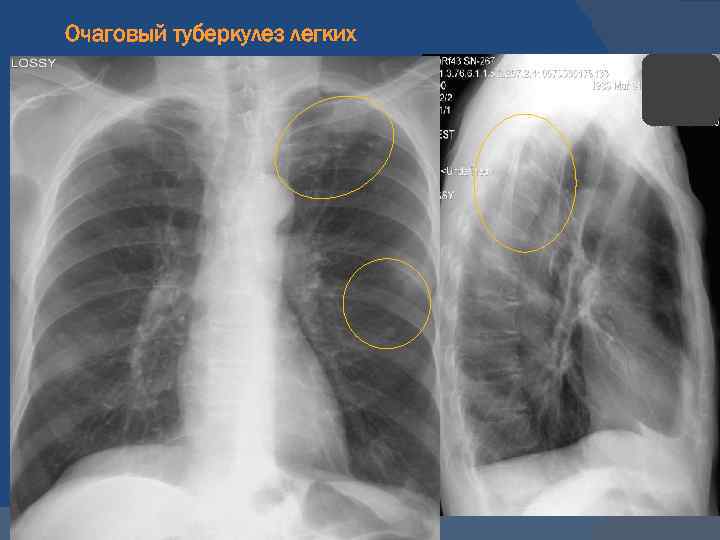

Иллюстрации по теме очагового и инфильтративного туберкулеза